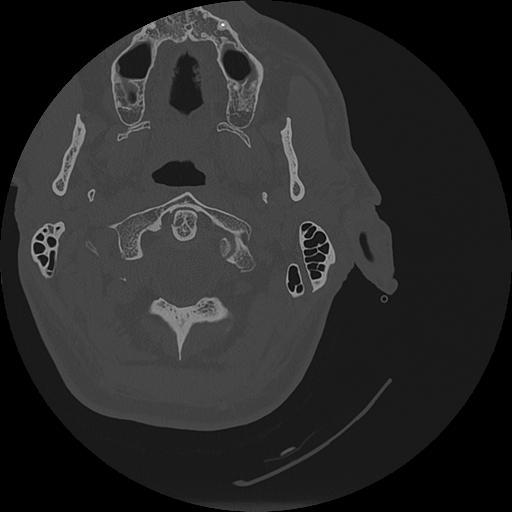

7 HUESO,,Vol,0.5,HUESO,,